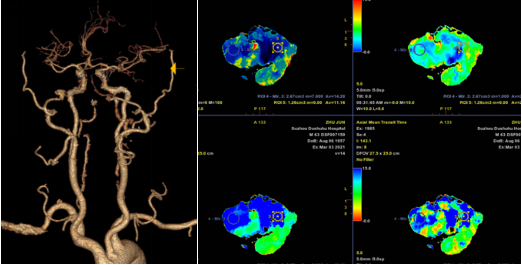

六十多岁的朱先生因“头晕19小时意识不清2小时”来到我院急诊,急诊神经科医师接诊后考虑脑血管疾病,立即行头颈部CTA+CTP检查,判断闭塞血管及梗死面积。影像科张卫国主任团体第一时间完成头颈CTA+CTP后处理,结果提示患者左侧椎动脉V1段起始处次全闭塞,右侧椎动脉V4段闭塞;基底动脉闭塞;双侧椎动脉供血区(双侧小脑、脑干、部分颞叶)缺血性灌注异常。

由于患者错过了4.5小时脑卒中静脉溶栓救治时间,无法溶栓治疗。郝永岗副主任带领神经血管介入团队评估病情后决定在全麻下为患者实施动脉取栓术,挽救处在缺血状态尚未坏死的脑组织。麻醉科李健主任第一时间到达导管室,保障手术顺利进行,术中可见患者基底动脉末端闭塞(基底动脉尖综合征)。医生运用SWIM技术取出黑红色血栓,复查造影显示:基底动脉远端血流通畅,双侧大脑后动脉、小脑上动脉显影。术中发现患者左侧椎动脉起始部重度狭窄,于病变处植入支架一枚,血管狭窄解除,术后送重症医学科继续治疗。